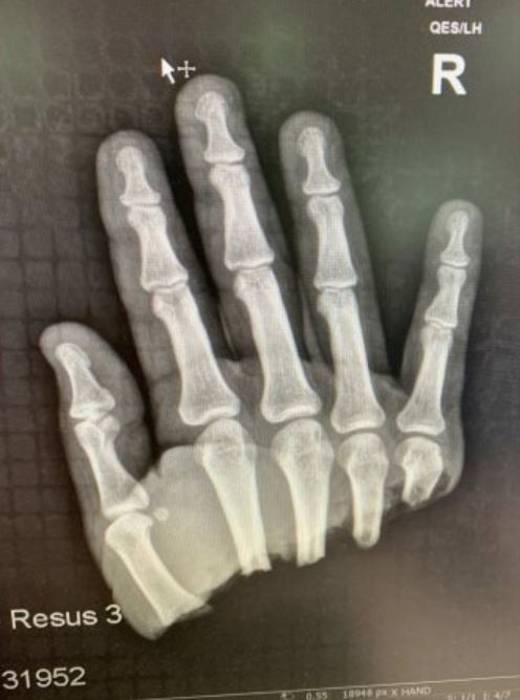

Lawrence was taken for surgery without wasting any precious moment and Dr. Theo Birch operated on him for 7 long hours just to make sure his hand is rejoined.

Doctor Theo said, “The surgery was not an easy one. It takes a lot to rejoin a hand. There is a mix of veins and arteries and it is important to join the right blood supply to the right one.

I first had to screw the bones together then only I could go on to untangle the blood supply and join them back together.”

Well, the surgery was a successful one as, within a day of surgery, Lawrence was able to wiggle his finger.